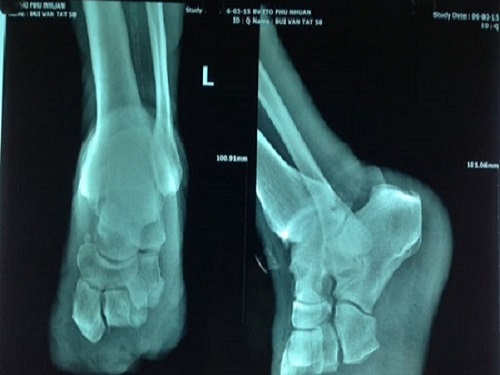

Khi xương bị vỡ, các thiết bị y tế và các đồ vật như ốc vít và ghim thường được sử dụng để cố định các mảnh vỡ lại với nhau trong khi xương đang lành. Nhưng quá trình này cực kỳ đau đớn, mất nhiều thời gian và vô cùng khó khăn. Tuy nhiên, một công nghệ mới kỳ diệu có thể khiến phương pháp nói trên trở nên lỗi thời. Công cụ mới có khả năng thay đổi một lĩnh vực y khoa này là phương pháp cấy ghép bằng gốm in 3D. Nó giúp nối các miếng xương bị gãy lại với nhau và sau đó chuyển thành xương tự nhiên.